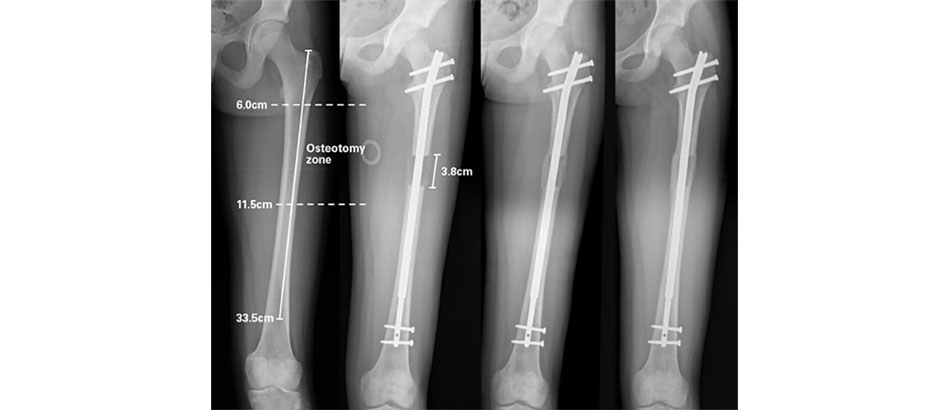

Kaza veya hastalık neticesinde kısa kalan bacakları uzatma konusunda yeni teknik ile geçtiğimiz yıl İngiltere’de ilk ameliyatı yapan Dr. Güryel, “Eskiden aylarca süren, enfeksiyona, ağrıya yol açan, hastaları yatağa veya eve bağlayan ameliyat yerine, özel “ intra modüler çivi” yöntemiyle yaptığımız ameliyatlar hem başarıyla sonuçlanıyor. Hem zamanı kısaltıyor, hem de hastamızın kısa bacağını eski boyutuna az ağrılı, sıkıntısız şekilde getiriyor” dedi.

Şimdi 5 yıl önce geliştirilen bir teknik ile kemiğe yerleştirilen “intra modüler çivi”, magnet yani mıktanıs ile günde 2-3 defa çevrilerek bu uzatmayı gerçekleştiriyoruz. Uzatmayı eski tekniğin aynı süresi içinde gerçekleştirsek de en önemlisi hasta bacağında çelik çerçeve ile gezmiyor. Çerçeve tamamen ortadan kalkıyor. Ağrı çok daha az, hareket etme daha kolay. Hastalar bu yöntemle çok daha başarılı, ağrısız, daha konforlu bir iyileşme geçiriyor. Çok daha rahat yürüyebiliyor. Bu yöntemle kaybolan kemik dokusu yerine geliyor, bacağı kaybolan ölçüde yerine getirebiliyoruz”

“Çeşitli nedenlerle bacağınızdan kemik kaybı yaşamışsınız. O zaman kemik taşıma yöntemini uyguluyoruz. Örneğin 5 santimlik kemik kaybolmuş. Aynı kemikte 5 santimlik kemiği kesip, boşluğu dolduruyoruz. Kemiği bir şekilde aşağı doğru itiyoruz ve zamanla kemik dokusu doluyor. Kemik kaybı olan kanserli hastalara da bu yöntemi uyguluyoruz. Eğer uzatma işlemi yapıyorsak intra modüler çivi kullanıyoruz. Bu çiviyi kullanarak kemiği aşağı doğru itebiliyoruz. Bu yöntemi 2 yıl önce geliştirdiler. Magnet kullanarak, çiviyi günde 2-3 defa döndürerek uzatmayı gerçekleştiriyoruz.

İngiltere’de bu yöntemle ameliyatı ilk ben uyguladım. İlk ameliyat Amerika’da yapldı. Nuvasive adlı Amerikan firması bu yöntemi geliştirdi. Amerika’da bu yöntemle 2 ameliyat yapıldı, Dünyadaki üçüncü, İngiltere’deki ilk ameliyatı da ben yaptım. Sonuç oldukça başarılı oldu.”